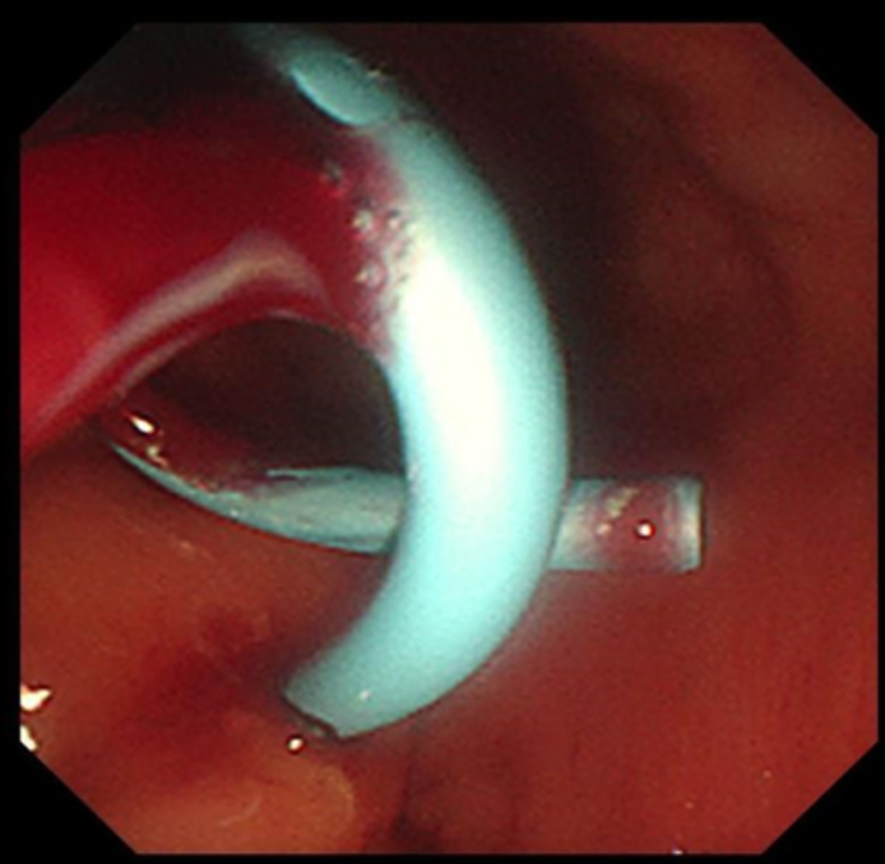

支架置入过程

经过充分的术前准备,消化内科刘华副主任医师在毛涛主任的指导下,和麻醉科、内镜室医护团队的密切配合下,凭借精湛的内镜技术,仅用时20分钟,便通过实时超声精准锁定病灶位置,巧妙避开血管、神经等重要解剖结构,合理规划穿刺路径并成功置入支架。手术全程经人体自然腔道操作,无体表切口,且未对直肠功能造成损伤。